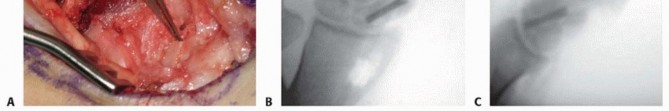

With the capsule open, the scaphoid nonunion site is brought into direct view. The nonunion is often obscured by fibrous scar tissue and a pseudarthrosis. Using a combination of a sharp dental pick, small curettes, and a high-speed burr, the fibrous tissue is meticulously debrided. The sclerotic bone ends of both the proximal and distal fragments must be resected back to healthy, bleeding, cancellous bone. The appearance of punctate bleeding—the "paprika sign"—confirms the viability of the fragments. Once debrided, the true extent of the volar bone void and the humpback deformity becomes glaringly apparent.

Correction of the humpback deformity is the most crucial biomechanical step. Two 0.045-inch Kirschner wires (K-wires) are inserted as joysticks: one into the distal scaphoid fragment and one into the proximal fragment. By applying an extension moment to the distal joystick and a flexion moment to the proximal joystick, the scaphoid is hinged open volarly. This maneuver restores the anatomical length of the scaphoid, corrects the lateral intrascaphoid angle, and simultaneously realigns the lunate out of its DISI posture. The resulting trapezoidal void on the volar aspect of the scaphoid is then precisely measured using a sterile caliper to determine the exact dimensions required for the bone graft.